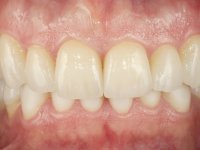

Realizado o diagnóstico e tomada a decisão quanto ao tratamento a executar, tornou-se importante definir qual a sequência de trabalho a adotar no sentido de conseguir a reabilitação da D.V.O. (V.D.O), de forma progressiva e equilibrada. Na primeira fase fez-se uma pré-impressão da arcada inferior com silicone tipo “putty” e em seguida realizou-se o preparo dentário de todo o sector posterior. O preparo para os overlays foi feito coronalmente à linha amelo cementaria no sentido de ser o mais conservador possível. A impressão foi feita com técnica de dupla mistura após afastamento gengival realizado com pasta de caulino. A provisória foi realizada com resina composta de polimerização dual. Em laboratório foram realizados os overlays após se ter aberto ligeiramente (1,5mm) a D.V.O. nos modelos montados em articulador semi-ajustável. Simultaneamente o sector antero-inferior foi encerado no sentido de acompanhar este aumento da D.V.O. Também foi confecionada uma chave de silicone translucido para posterior confeção dos provisórios antero-inferiores. Em boca foi primeiro realizada a provisionalização dos dentes anteriores utilizando resina composta previamente aquecida após preparação das superfícies dentárias para a adesão. Foi colocado o dique de borracha para promover o isolamento absoluto e posteriormente foram colados os overlays. Em laboratório foi realizada nova chave de silicone para confecionar os provisórios antero-superiores. Seguidamente em boca foram preparados os seis dentes antero-superiores após colocação do fio de afastamento gengival. Feita a preparação adequada das superfícies dentárias foi realizada a impressão com técnica de dupla mistura e a respetiva provisória. Em laboratório foram confecionadas 6 facetas feldespáticas num modelo de trabalho tipo “Geller”. A provisória foi removida e as facetas foram coladas em boca utilizando um isolamento relativo competente. Esta opção foi tomada em virtude de uma prévia experiencia negativa com a colocação do dique de borracha na mandibula. Após a colagem dos laminados antero-superiores foram dadas 12 semanas para avaliar a adaptação do paciente à nova situação e então iniciar a confeção das facetas antero-inferiores. Após colocação do fio de afastamento gengival. foram feitos os preparos dentários adequados e em seguida foi feita a impressão. Também foi feita a preparação do dente 3.4 que, entretanto, tinha sofrido uma fratura do overlay. As facetas e a restauração do 3.4 foram realizadas num modelo de trabalho tipo “Geller”. Após remoção da provisória, as facetas foram coladas em boca, utilizando um isolamento relativo pelas razões apontadas anteriormente. Após colocação do trabalho o paciente foi reabilitado por outros colegas com um implante na zona do 2.6 e substituição da coroa aparafusada sobre o implante colocado no local do 3.5. Posteriormente surgiram fraturas nos overlays dos dentes 4.7 e 3.7 que foram reabilitados com overlays em Zr.